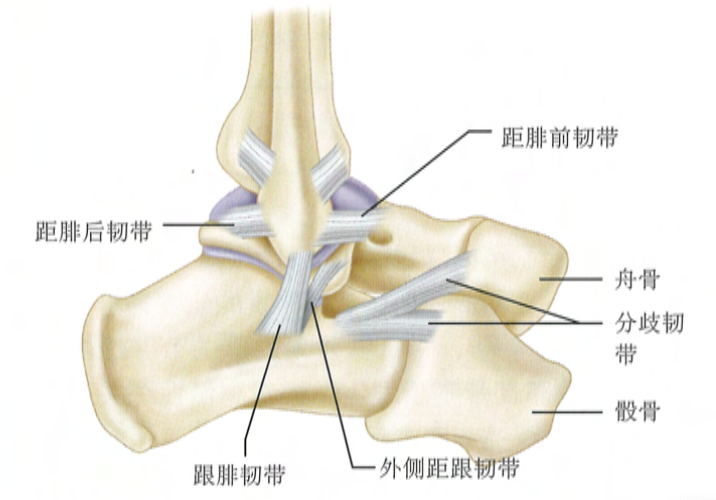

踝关节骨折,骨折块越小越有可能合并韧带损伤,如果不注意处理,后期关节不稳,创伤性关节炎极易发生。文章结合 4 个典型病例,带大家认识踝关节的小骨折、大麻烦!

人体的踝关节,既要承重,又要灵活。这里韧带丰富,肌腱迂回,血管、神经深入浅出。还是那句话,累及关节的手术做得再好都不过分!